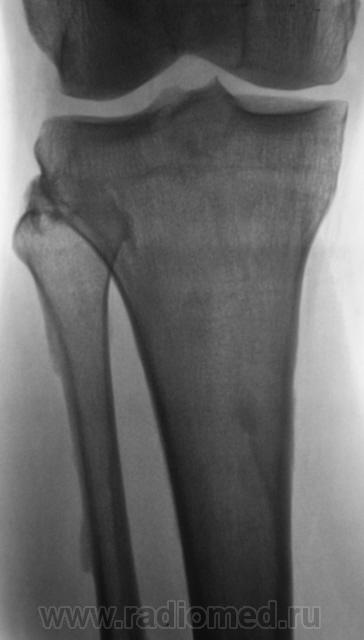

Мужчина средних лет, крепкий, ведущий активный образ жизни, занимающийся дозировано «элементами спорта», полковник милиции, в последнее время (несколько лет) почувствовал боли в области правого коленного сустава.

Энтезопатия надколенника, перегрузочная болезнь б/б кости(подозрение на неполный перелом).

Очень похожая картина на консолидированный перелом б\б кости. В проекции м\б кости определяется периостальная реакция или патологическая перестройка костной ткани.

Есть  признаки  артроза  и  синовита . Была  повреждена  передняя  крестообразная  связка.

Боли почти постоянные, усиливаются после физической нагрузки.